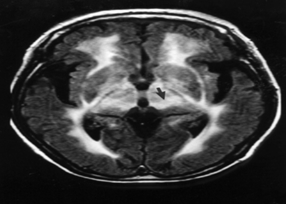

피질하 경색과 백질뇌증을 동반하는 상염색체 우성 뇌동맥질환(Cerebral Autosomal Dominant Arteriopathy with Subcortical Infarcts and Leukoencephalopathy)